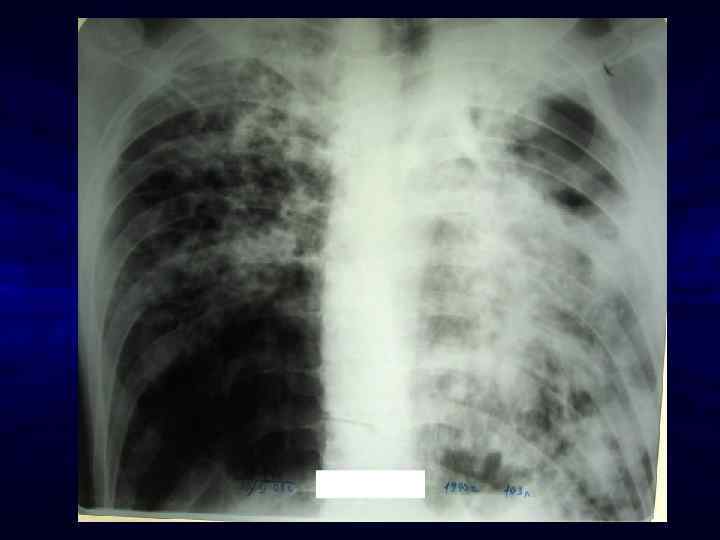

Этиология вторичных заболеваний у больных ВИЧ-инфекцией, госпитализированных в ИКБ № 2 г. Москвы в 2013 -2015 гг. • • • • Всего 10915 больных, из них 4145 (38%) - на стадии СПИДа Из 4145 больных на стадии СПИДа Туберкулез 1498 (36, 1%) Висцеральный кандидоз 1089 (26, 3%) Манифестная ЦМВ-инфекция 669 ( 16, 1%) М/энц н/э (вкл. ВИЧ-энцефалит 557 (13, 4%) Пневмонии возвратные 442 (10, 7%) Пневмоцистная пневмония 437 (10, 5%) Токсоплазмоз 251 (6%) Лимфопролиферативные заболевания 96 (2, 3%) Саркома Капоши 87 (2, 1%) Атипичный микобактериоз 38 (0, 9%) Мультифокальная лейкоэнцефалопатия 35 ( 0, 8%) Рак шейки матки 19 (0, 5%) Криптококковый менингит /генер. криптоккоз 18 (0, 4%)/7 (0, 1%) Криптоспоридиоз кишечника 14 (0, 3%) ВПГ-бронхит/пнвемония, генерал. сальмонеллез - единичные случаи

Лимфома ЦНС у больного ВИЧ-инфекцией